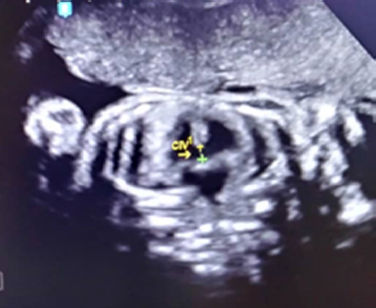

Se trata de paciente femenina de 19 años, sin antecedentes familiares, personales y patológicos conocidos, IV gestas, II cesáreas, I aborto, FUR 18/08/2018, quien acude a especialista en medicina materno-fetal y en vista de hallazgos ecográficos es referida a la Unidad de Perinatología y Medicina Materno-Fetal del Hospital Materno Infantil Dr. José María Vargas, siendo evaluada el 13 de febrero de 2019, donde se realiza estudio ultrasonográfico Perinatal en tiempo real, con transductor convex de 3,5 mHz, ecógrafo marca Esaote, visualizándose estructuras fetales compatibles con dos fetos que correspondían a un embarazo múltiple doble, se identificaron ambos polos cefálicos ubicados en el mismo plano de corte durante la exploración (Figura 1), 4 extremidades superiores, tórax y abdomen de ambos fetos fusionados, corazon único (Figura 2), de difícil evaluacion, impresionando defecto septal ventricular de 4,6 mm (Figura 3), 2 cámaras gástricas (Figura 4), 2 vejigas, sexo femenino, 4 extremidades inferiores, una sola placenta anterior, grado I, grosor 42 mm, con índice de líquido amniótico (ILA) máximo bolsillo vertical (MBV) de 43 mm. Concluyéndose estudio ecográfico con diagnósticos de: Embarazo múltiple doble monocorial monoamniotico (Duplicata completa: siameses toracoonfalopago) de 25 semanas más 4 días por fecha de ultima menstruación con corazon único asociado a posible comunicación interventricular (CIV) sub-aortica.